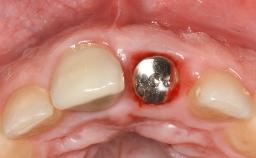

Peri-Implant Mucositis Treatment Outcomes on an Implant with a Submucosal Restoration Margin

Mauricio Araujo and Flauvia Matarazzo present this straightforward clinical case, demonstrating the potential effect of implant placement depth on the resolution of peri-implant treatment. A 42-year-old systemically healthy female patient, a non-smoker with no history of periodontitis, was treated at the Dental Clinic at the State University of Maringá, Brazil between 2008 and 2009, when she received five implants restored with single crowns at sites 14, 26, 27, 36, and 46. After delivery of the implant-supported prosthetic restorations, the patient was enrolled in the supportive peri-implant therapy (SPiT) maintenance program at the same university.